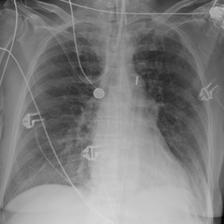

In this regard, VLP in biomedicine and radiology poses a distinctive challenge, as reports routinely include comparisons to prior imaging studies [47, 3, 57]. Without knowledge of this prior image111In the MIMIC-CXR v2 dataset [36], around 40% of reports explicitly reference a previous image. See Appendix B for details., temporal information in the text modality, e.g. “Pneumonia is improving”, could pertain to any image containing “Pneumonia”, producing ambiguity during contrastive training (Figure 1). Despite this, the existing VLP work to date considers alignment between only single images and reports [81, 32, 46, 9], going so far as to remove temporal content from reports in training data to prevent ‘hallucinations’ in downstream report generation[54]. However, temporal information can provide complementary self-supervision, solely by exploiting existing structure, and without requiring any additional data.

Table A.1 shows example reports generated with BioViL-T and BioViL models, which are compared to the reference radiologist’s reports. In comparison with BioViL which only models the current image, BioViL-T shows the benefit from incorporating prior study information and is able to provide factually more accurate reports especially in terms of describing temporal progression of the findings. This is showcased in the first two examples in the table: In the first row, BioViL-T is able to comment on not only the presence of the pleural effusion but also its improvement while BioViL fails to mention the change. In the second example, BioViL-T is able to correctly identify that there is no relevant change by comparing with the previous study, while BioViL wrongly hallucinates the tube in the current image as a new placement. BioViL-T can also avoid hallucination of the temporal information when there is no prior study. For instance, in the third example, BioViL-T correctly acknowledges that there is no prior image and generates the report based on information from the single current image, while BioViL hallucinates a non-exisistent prior study and wrongly generates temporal descriptions in the report.